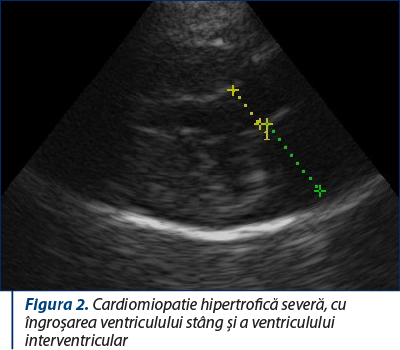

Figura 2. Cardiomiopatie hipertrofică severă, cu îngroşarea ventriculului stâng şi a ventriculului interventricular